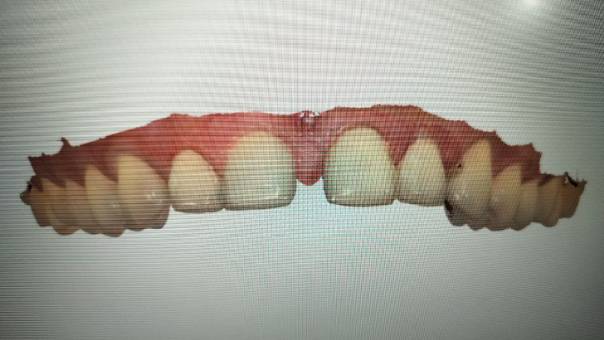

More significantly, the patient had a reverse curve in the upper anterior region—a condition where the natural curvature of the smile arch is inverted. This disrupted the overall smile aesthetics.

Treatment Plan:

Root Canal Treatment for all upper anterior teeth (from right canine to left canine) to manage any underlying pathology and provide a stable foundation for prosthetic work

Placement of Zirconia joined crowns across the anterior segment to restore form, function, and aesthetics

Smile designing using crowns to correct the reverse curve and improve facial harmony

The Smile Transformation: Zirconia crowns were chosen for their superior strength and excellent esthetics, allowing us to achieve a lifelike appearance with high durability. The crowns were custom-shaded to match the patient’s natural teeth, eliminating the previously noticeable mismatch.

Through careful planning and execution of smile design principles, we successfully reversed the unnatural curvature of the upper anterior arch. The result was a balanced, harmonious smile that significantly enhanced the patient's overall appearance.